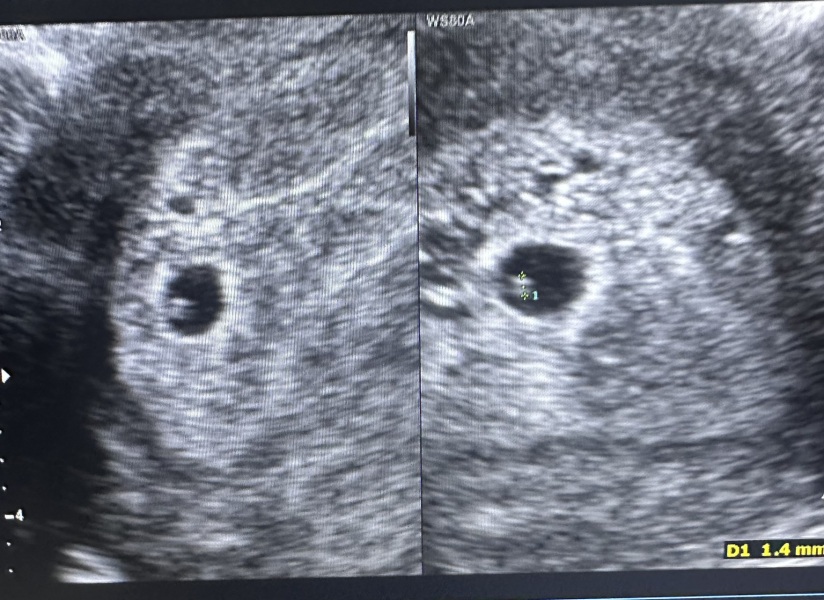

5 week 1 day scan

The doctor was lovely, he said I was 5weeks 1 day pregnant and that he wouldn't hear a heartbeat as I'm too early and need to come back in 2 weeks, he confirmed I was pregnant and I came out feeling relieved and happy.

Then I got home and started to read my report and it's says " no clear yoke sac or FT " tbh I didn't even know what that was, I started googling and tik tok and I'm now in sheer panic because I'm reading I should have a yolk sac at this point in my pregnancy and this could be a sign of a void pregnancy. I can't stop crying.

When I look at other images with no yolk sac I don't see anything in them but I'm sure mine has one, he never commented on the little circle inside the sac.

Don't panic! That's so early to be having a scan! He didn't say there definitely wasn't one, just that it wasn't "clear". He's clearly taken note of what you're referring to as he's measured it! I had a scan at 5+4 in a previous pregnancy to check placement (after a previous ectopic) and saw a yolk sac but no fetal pole. They said that days make a huge difference in terms of what can be seen when you're so early on. Chances are you'll go back in a week and see much more! X

As everyone wlse has mentioned its way too early to assume thing's aren't developing as they should be. Also the scan photo does seem to show something in the sac i dont think many even get that so early. Try to relax